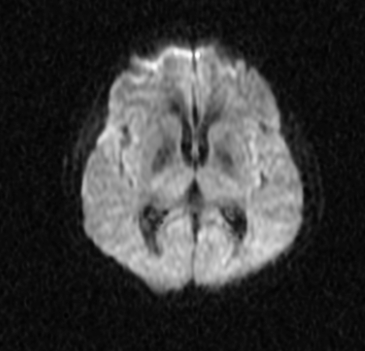

In this study, we aim to initiate the development of Radiology Foundation Model, termed as RadFM.We consider the construction of foundational models from the perspectives of data, model design, and evaluation thoroughly. Our contribution can be concluded as follows: (i), we construct a large-scale Medical Multi-modal Dataset, MedMD, consisting of 16M 2D and 3D medical scans. To the best of our knowledge, this is the first multi-modal dataset containing 3D medical scans. (ii), We propose an architecture that enables visually conditioned generative pre-training, allowing for the integration of text input interleaved with 2D or 3D medical scans to generate response for diverse radiologic tasks. The model was initially pre-trained on MedMD and subsequently domain-specific fine-tuned on RadMD, a radiologic cleaned version of MedMD, containing 3M radiologic visual-language pairs. (iii), we propose a new evaluation benchmark that comprises five tasks, aiming to comprehensively assess the capability of foundation models in handling practical clinical problems. Our experimental results confirm that RadFM significantly outperforms existing multi-modal foundation models. The codes, data, and model checkpoint will all be made publicly available to promote further research and development in the field.